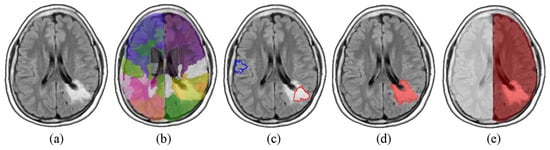

In analogy to what was accomplished by Soltaninejad et al. [], the SVM was fed with a set of 14 texture features computed on each region (i.e., average, standard deviation, variance, mean and median of the absolute deviation, skewness, kurtosis, maximum, minimum, median and mode of the intensity values, range, interquartile range, and entropy). The classifier was then tested on the whole dataset giving out a three-dimensional mask (Vt), for every image, containing the affected volume. The position of Vt allowed us to identify the hemisphere in which each lesion was predominantly located. All these steps are illustrated in Figure 1.

Figure 1.

Steps (axial sections) of the procedure for the preliminary tumor mass localization. Each FLAIR image is mapped onto the MNI space (a), and (b) parcelled into ~300 districts (different colors identify different areas). In (c) clear training regions for SVM are selected (typical healthy and affected tissue outlined in blue and red respectively), and in (d) all the areas classified as diseased are merged together in a volume (Vt, in red). Final decision of the tumor-affected hemisphere (right hemisphere, highlighted in red), by intersecting Vt with a coarse mask of the two hemispheres (e).

Notably, the SVM classification was not used to segment the tumor. Rather, it was only used as seed to define the affected and non-affected brain hemisphere. Therefore, segmentation accuracy is not a concern as any coarse segmentation would serve the purpose.